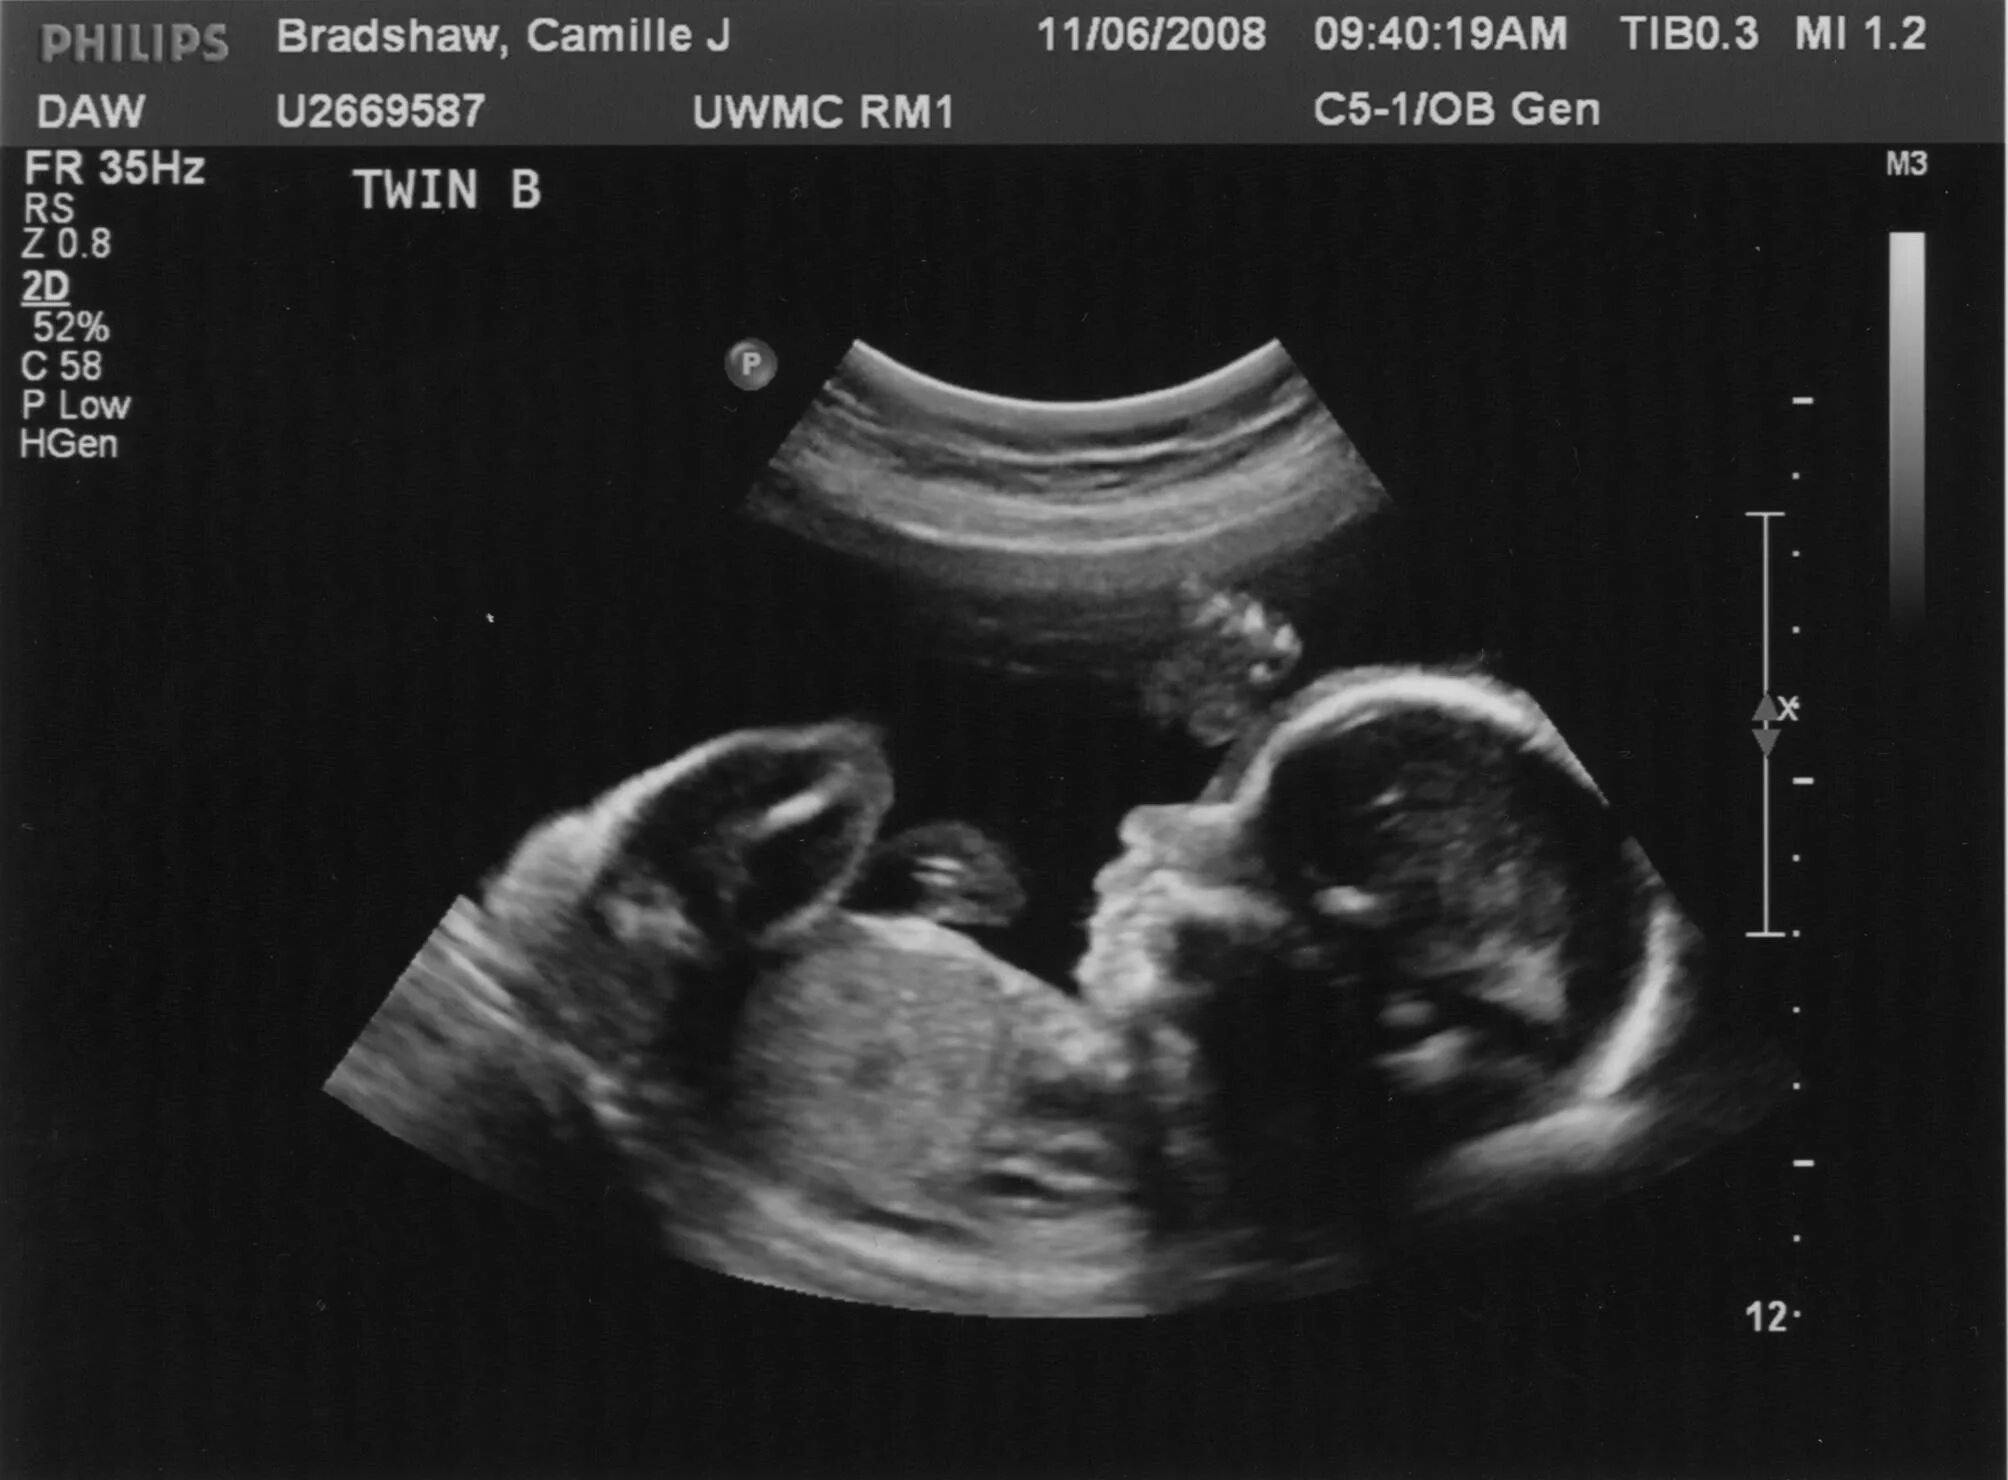

25 недель 2 дня